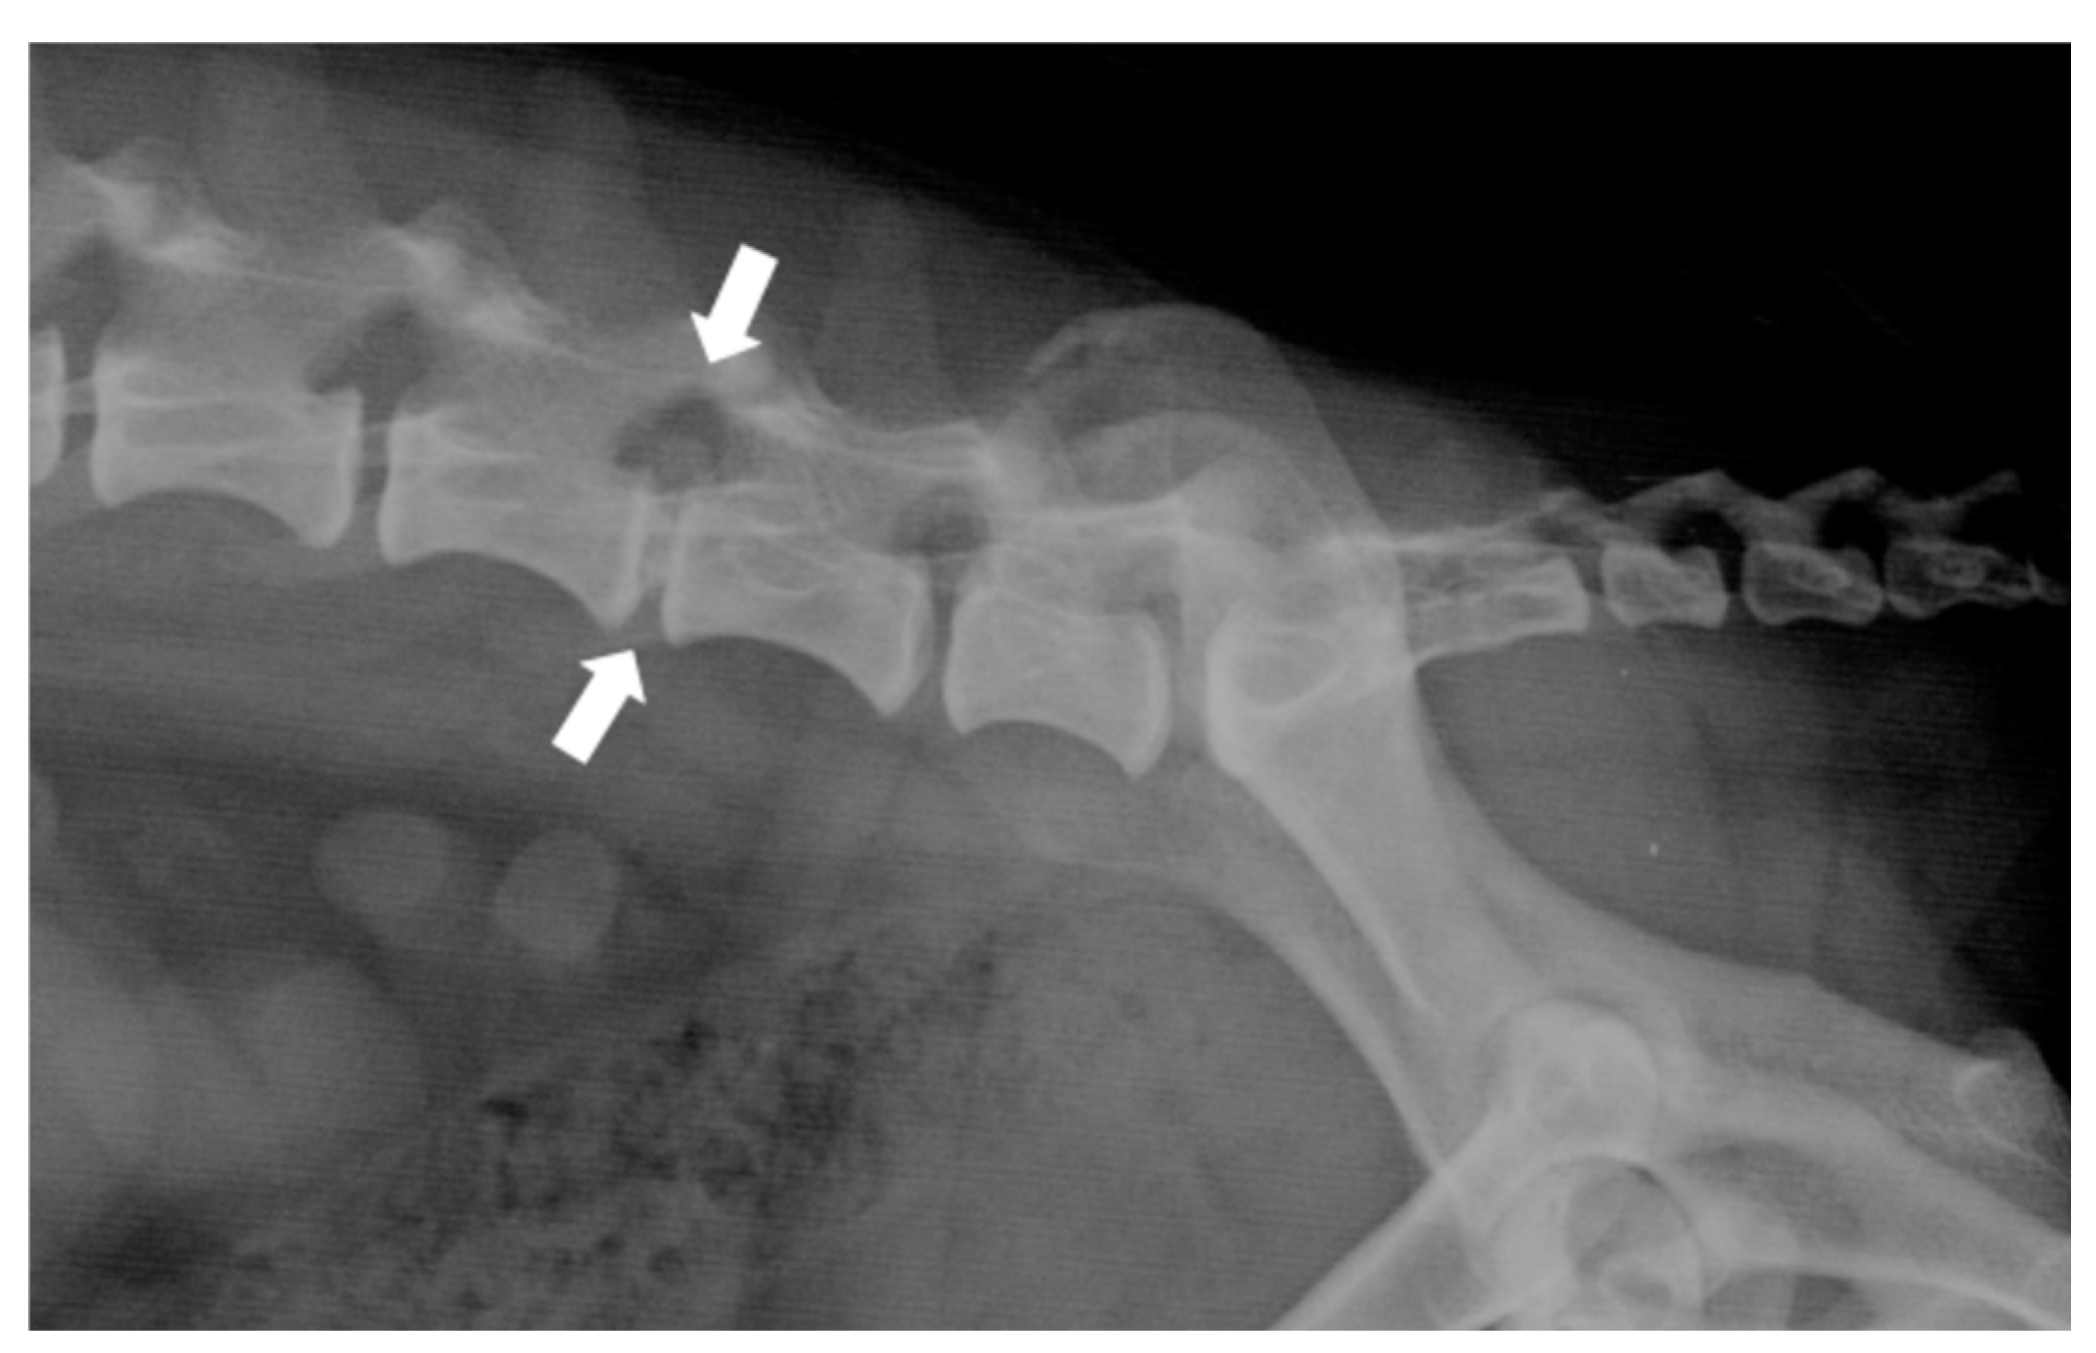

- Harder, L. K. (2016). [Diagnostic imaging of changes of the canine intervertebral disc]. Tierarztliche Praxis. Ausgabe K, Kleintiere/Heimtiere, 44(5), 359–371. [CrossRef]

- da Costa, R. C., De Decker, S., Lewis, M. J., Volk, H., & Canine Spinal Cord Injury Consortium (CANSORT-SCI). (2020). Diagnostic Imaging in Intervertebral Disc Disease. Frontiers in Veterinary Science, 7, 588338. [CrossRef]

- Robertson, I., & Thrall, D. E. (2011). Imaging dogs with suspected disc herniation: Pros and cons of myelography, computed tomography, and magnetic resonance. Veterinary Radiology & Ultrasound: The Official Journal of the American College of Veterinary Radiology and the International Veterinary Radiology Association, 52(1 Suppl 1), S81-84. [CrossRef]